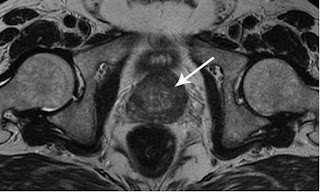

La prostatite se manifeste principalement par des troubles de la miction. Ce symptôme prédominant est souvent accompagné de sensations de brûlure lors de la miction. Ce trouble se traduit par une difficulté à commencer à uriner, une diminution de la force du jet urinaire, et une sensation que la vessie n'est jamais complètement vide. Les patients peuvent ressentir des besoins fréquents et urgents d'uriner, surtout la nuit, ce qui perturbe leur sommeil et affecte leur qualité de vie. 🔧

Outre les troubles de la miction, la prostatite présente une gamme de symptômes variés qui peuvent considérablement altérer le bien-être général et la vie quotidienne des hommes affectés. Parmi ceux-ci, on trouve :

Guérit la prostate 📋

Men's Defence aide les cellules et les organes affectés du système génito-urinaire à retrouver leurs fonctions naturelles. En restaurant la circulation sanguine normale dans la région du petit bassin, il contribue à la guérison de la prostate et au retour à une vie sexuelle normale. Les résultats sont durables, offrant aux patients une solution à long terme pour leurs problèmes de prostate.